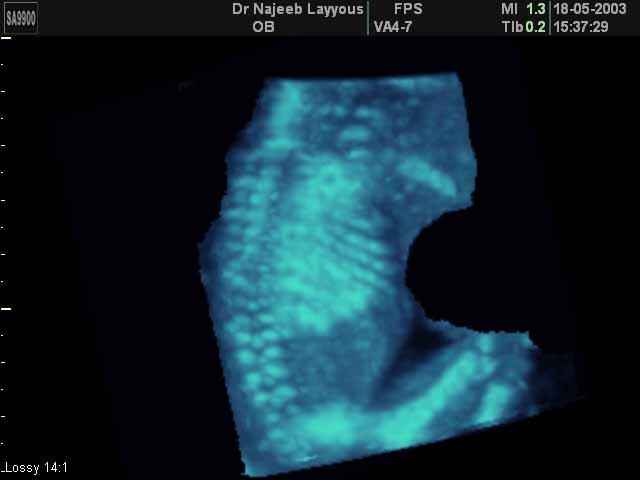

- صور للهيكل العظمي للجنين

صور للهيكل العظمي للجنين بجهاز الالتراساوند ثلاثي الأبعاد | الدكتور نجيب ليوس